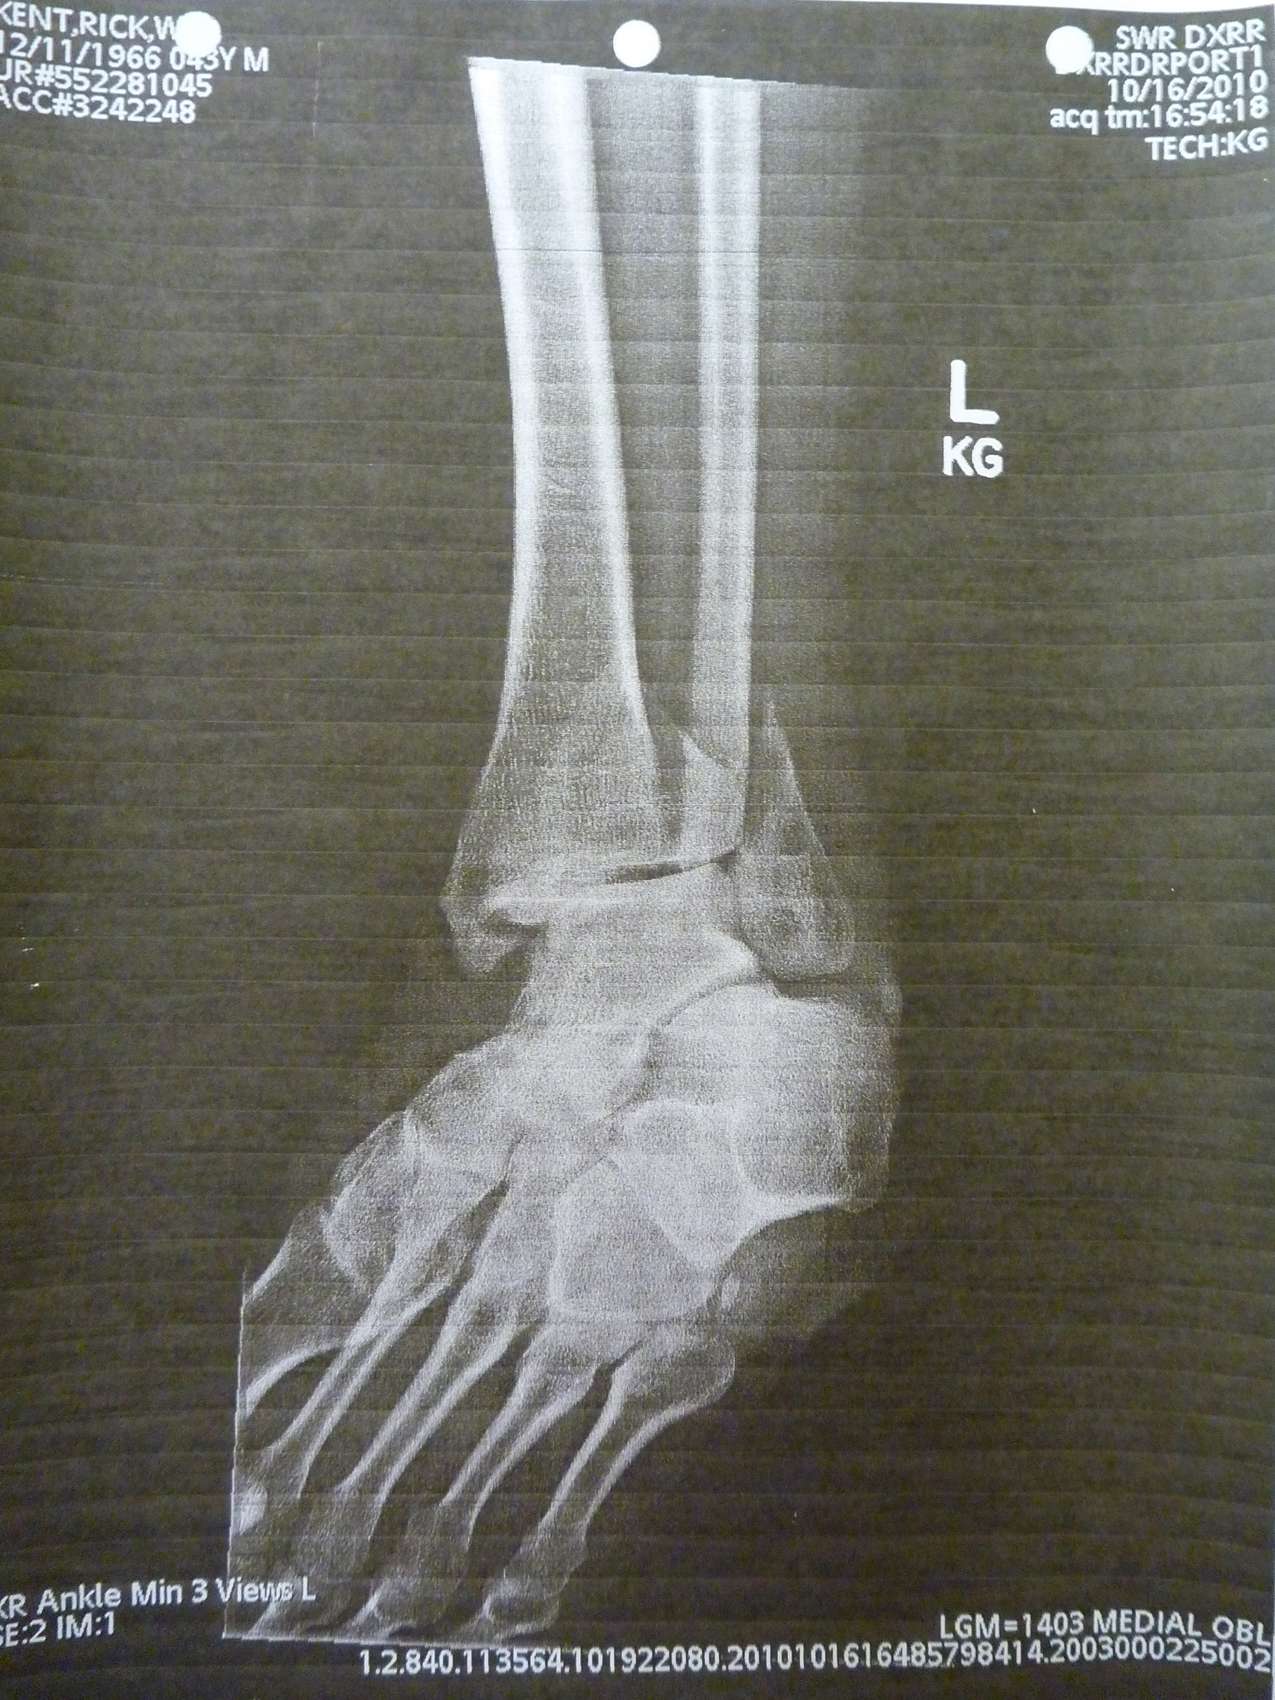

Album: Accident Photos: X-rays

Album Date

10/16/2010